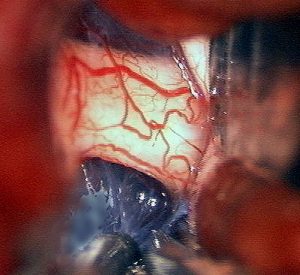

眼窩内単視神経膠腫

1歳児の左眼窩内単視神経膠腫です。左目は手動弁程度ですから,全摘出しました。まぶたの動きと眼球運動は温存しました。この例に何年も化学療法を続けるのは馬鹿げています。

左の写真は,左眼窩内腫瘍,右の写真は,頭蓋内の正常左視神経です。